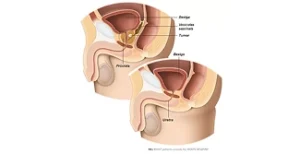

dos homens acima de 50 anos apresentam algum grau de Hiperplasia Prostática Benigna (HPB) — mesmo sem sintomas no início.

dos homens acima de 50 anos apresentam algum grau de Hiperplasia Prostática Benigna (HPB) — mesmo sem sintomas no início.

Técnica endoscópica avançada que remove o tecido prostático obstrutivo com mínimo sangramento, ideal para próstatas volumosas, substituindo cirurgias abertas convencionais.

Cirurgia robô-assistida para remoção completa da próstata e vesículas seminais, garantindo alta precisão, menor sangramento e melhor preservação da continência urinária e função sexual.

Indicação para próstatas extremamente aumentadas, permitindo excelente visualização cirúrgica, menor trauma tecidual e recuperação mais rápida.